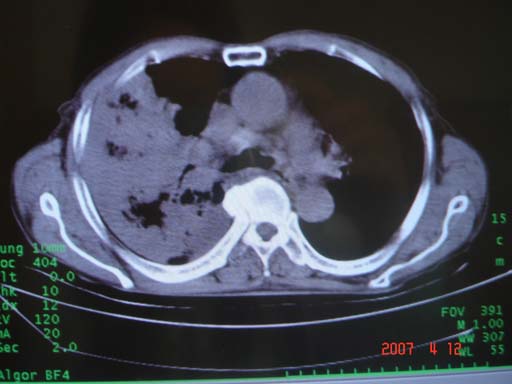

帮我 看看。男77岁咳嗽咯血2月发热2周!病人一般情况可 口痰为鲜红,有点象洗肉水(我看见他吐的痰了)

为何只有这么几幅图像?连纵隔窗都没有。但我发现上叶支气管显示不清,再加上年纪大,咯血等症状,恶性肿瘤首先得考虑。

考虑右肺新生物伴右中上肺阻塞性肺炎及含气不良,右侧胸腔积液。建议痰与纤支镜检查

考虑右侧中央型肺癌伴中上肺阻塞性肺炎、不张,胸腔积液。,建议支纤镜检查。

考虑:右上肺癌伴中上叶炎症,右侧胸腔积液。

病灶局限在右肺中上叶,呈大片状实变影,内见空气支气管征,支气管分支较柔软,纵隔内未见肿大淋巴结.支持:感染性病变_1 大叶性肺炎.2 干酪性肺炎.

优先考虑右上肺干酪性肺炎并同侧中叶播散、胸腔积液。分析:右膈肌未见升高、纵隔未见明显右移,胸部各组淋巴结未见可疑肿大,中叶可见支气管铸形,肺野、肺门未见可确定肿块。

右肺上叶后段支气管中断,首先考虑中央型肺癌并右肺不张及纵隔淋巴结转移,右侧胸腔积液。